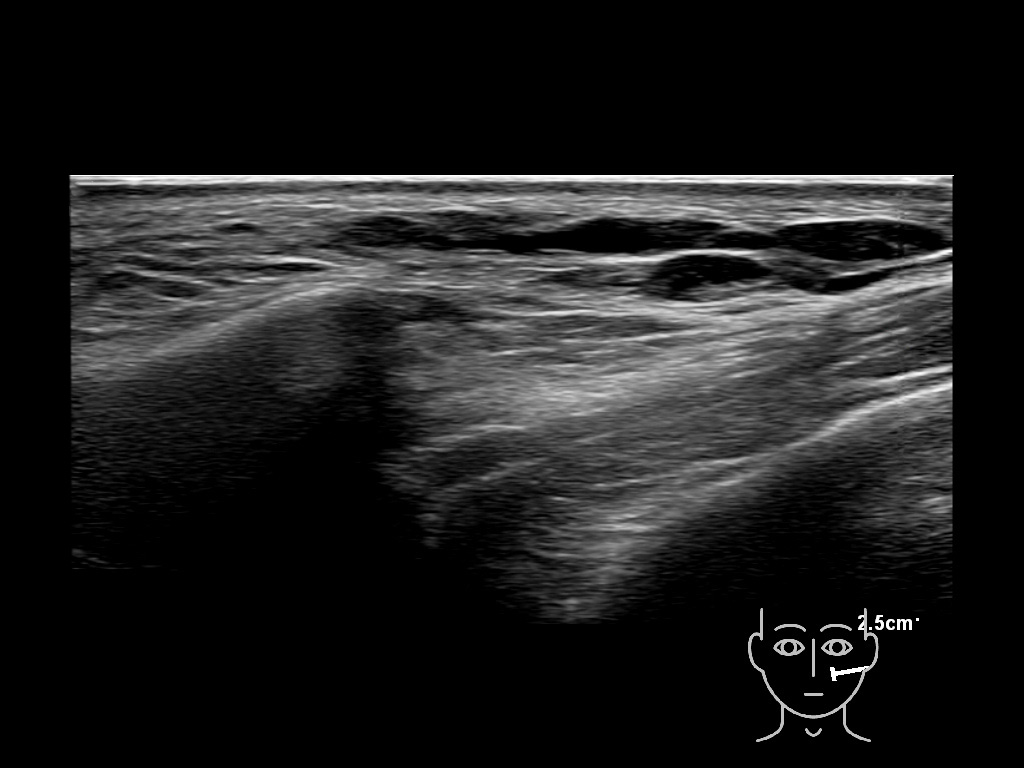

Filler behavior - Temple zygoma US

Study the first image to recognize the different layers. If you are sure about the layers, swipe to the second image to view the answer (if applicable).